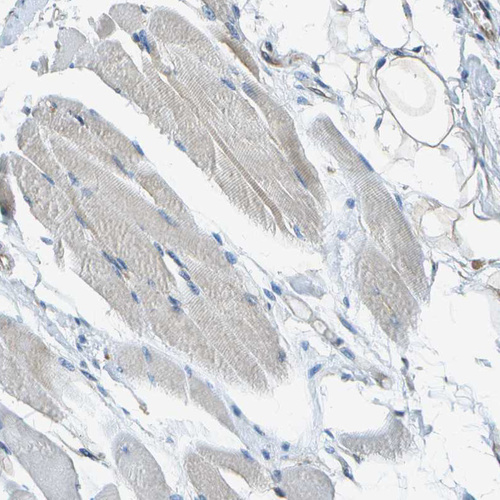

Immunohistochemical staining of human fallopian tube shows moderate cytoplasmic positivity in glandular cells and endothelial cells.